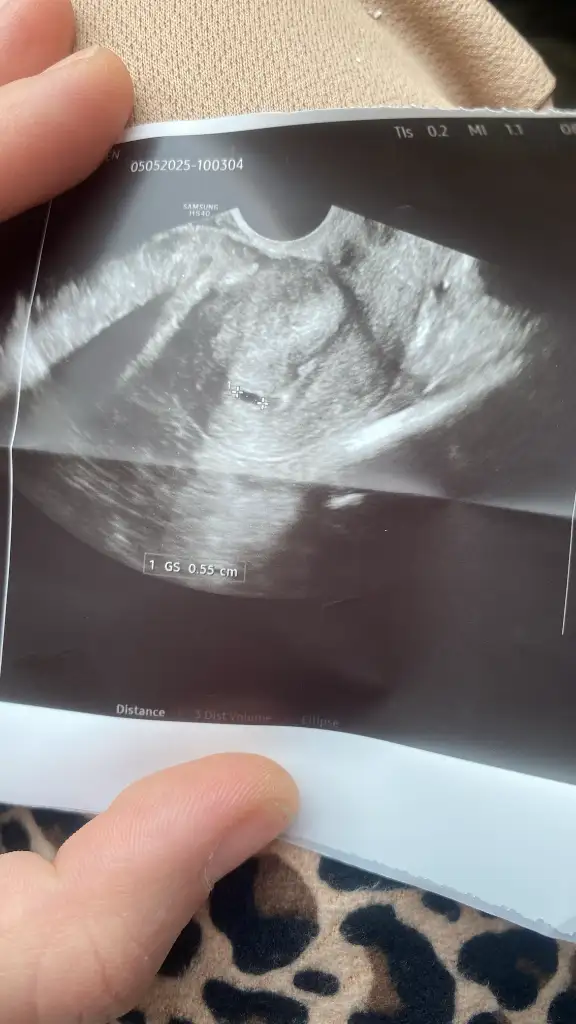

Benimkinede alttan baktı ama kaç haftalık olduğu yazmıyor ultrasyon kâğıdında ama seninkinde bebiş gözüküyor tektas gibi duruyor hayırlısı olsun bakalım 😇

Bilginiz var mı bilmiyorum ama tektaş şeklindeki yapı için yolk sac beslenme kesesi deniyor diye okumuştum bebekte o şekilde mi gözükecek peki ben daha görmedim